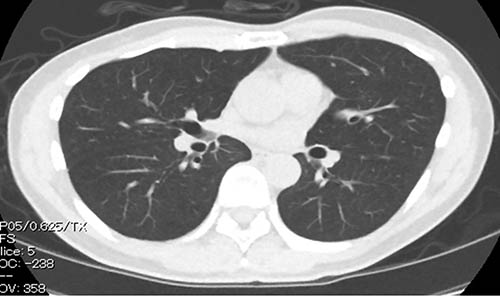

特点3:肺癌体检

- 我院体检中心调整摄影条件,导入低辐射的CT,可令体检者承受一般X光相当的辐射量即可接受CT检查。